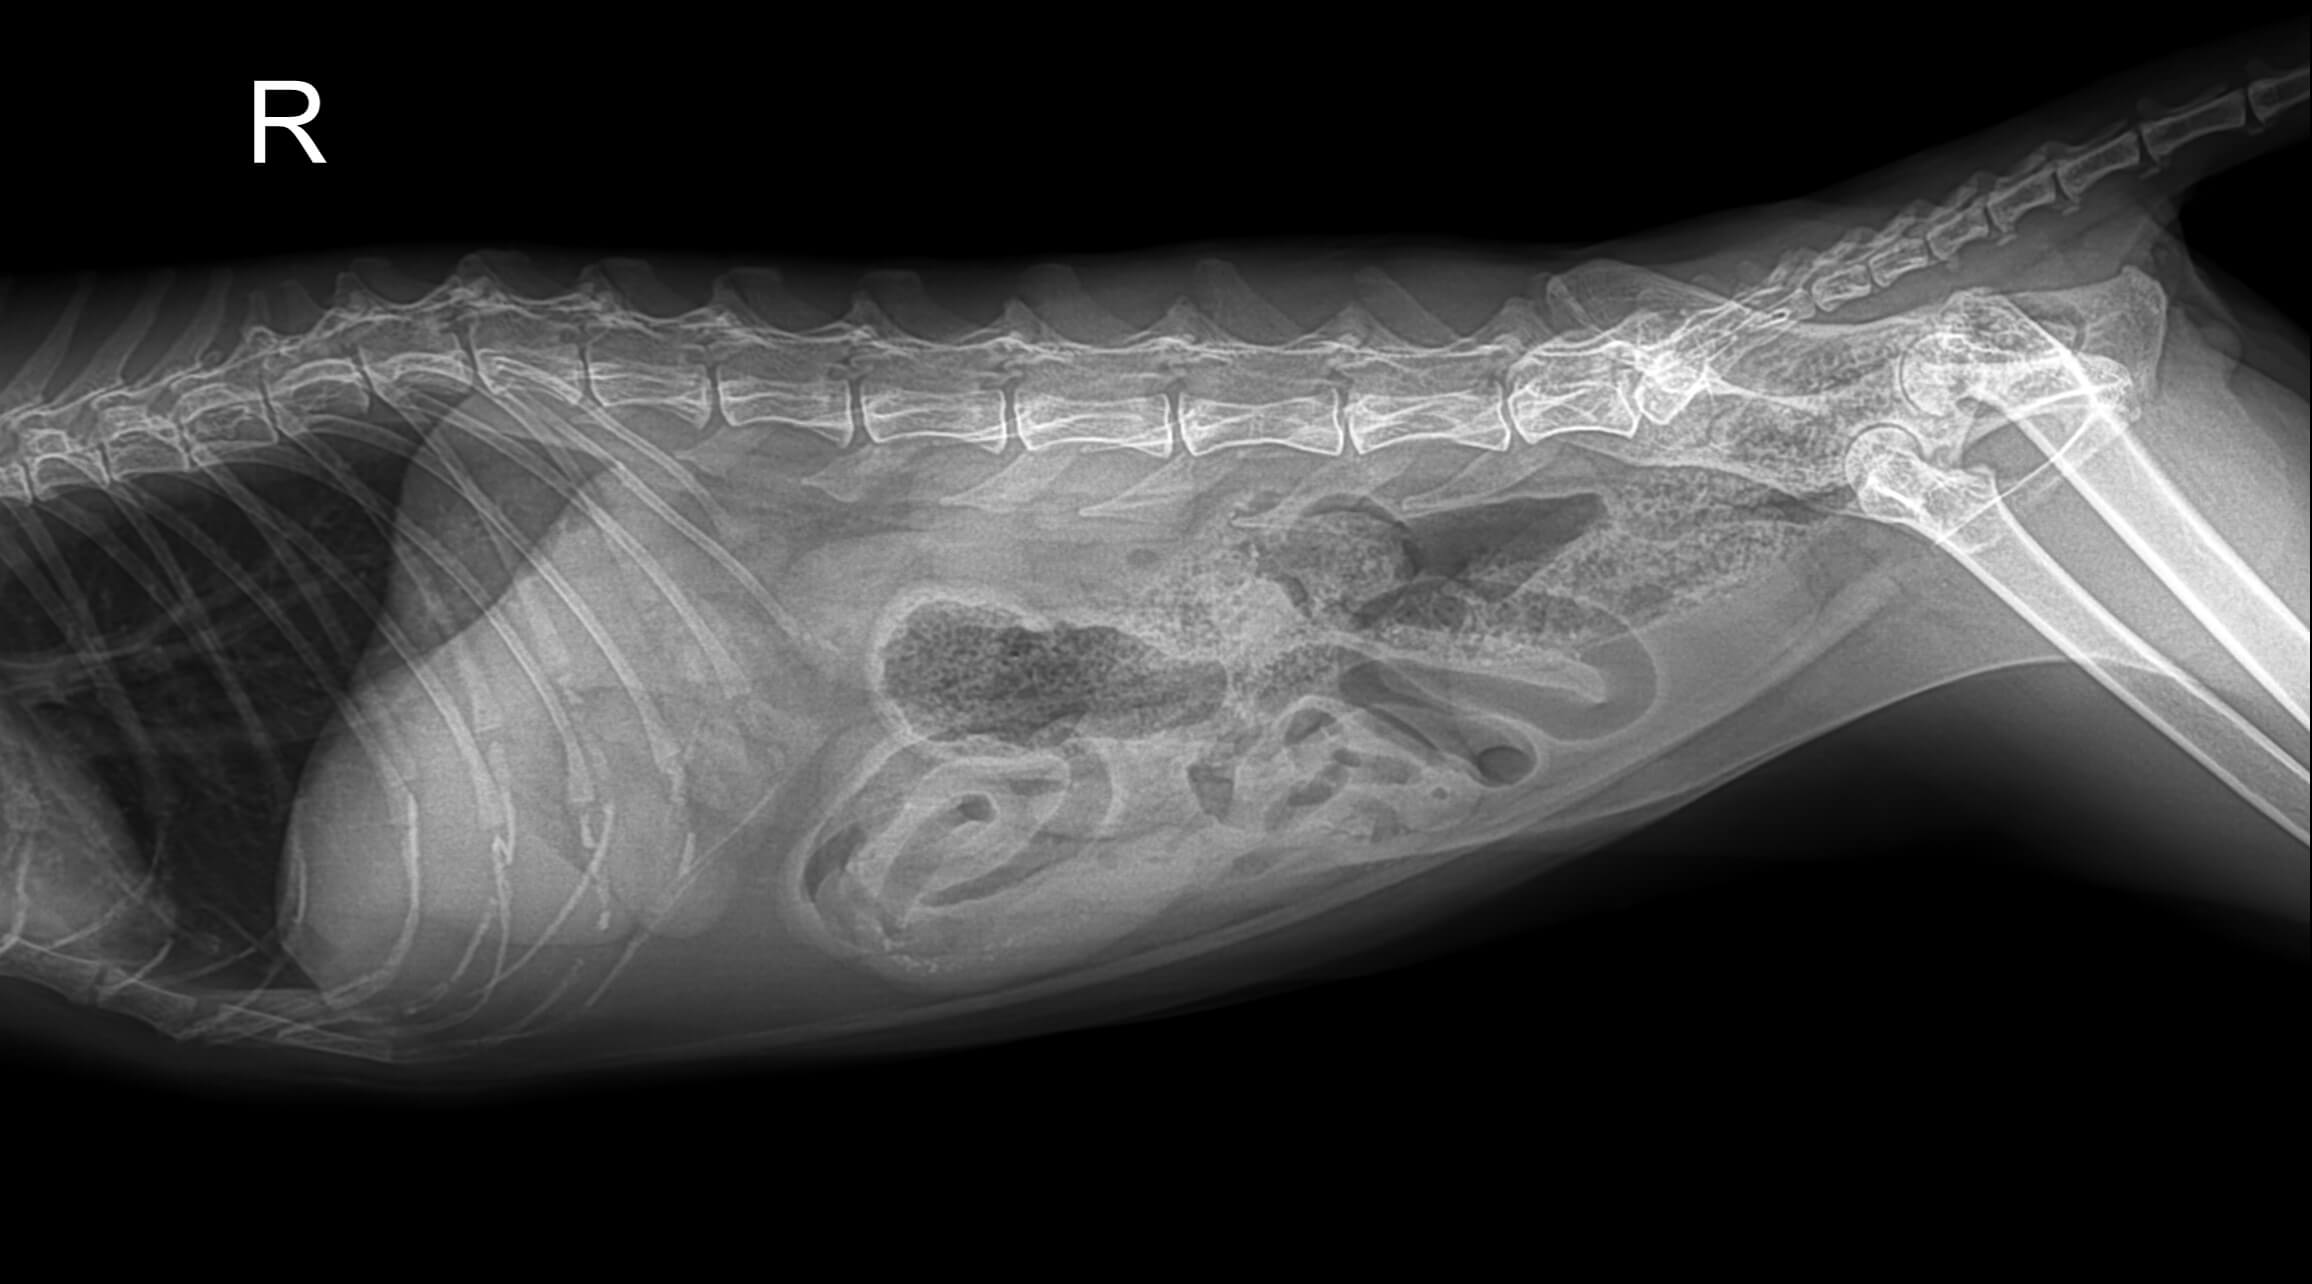

환자: 8세 중성화 수컷 버미즈 고양이

주호소: 2주간의 식욕 감소, 활동량 감소, 호흡 곤란

병력: 보호자가 약 6개월 전부터 직접 조리한 식이(닭고기, 쌀, 야채 위주)를 급여해왔으며, 상업용 고양이 사료는 거의 먹이지 않았습니다.

진찰 소견:

- 심한 호흡 곤란과 개구 호흡

- 청진 시 심잡음과 폐수포음 확인

- X-레이에서 심장 비대와 폐수종 확인

- 심초음파에서 심실 확장과 수축력 저하(박출률 25%) 확인

- 혈액 검사에서 타우린 수치 현저히 감소

진단: 타우린 결핍으로 인한 확장성 심근병증